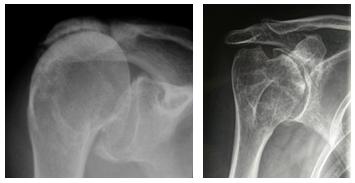

Una variante particolare di artrosi è quella che consegue a lesione massiva della cuffia dei rotatori, in cui l’omero risale verso l’alto perdendo la centrazione con la glena. Si parla di artropatia da lesione inveterata di cuffia (fig. 5).

Poi vi sono le malattie reumatiche (fig. 6) come l’artrite reumatoide, l’artrite psoriasica e altre; le necrosi della testa omerale (fig. 7), in cui una porzione della testa non riceve più apporto di sangue, degenera e si deforma (possono essere facilitate dall’uso di cortisonici e da varie altre condizioni); gli esiti di fratture mal consolidate (fig. 8) con deformazione dell’articolazione.